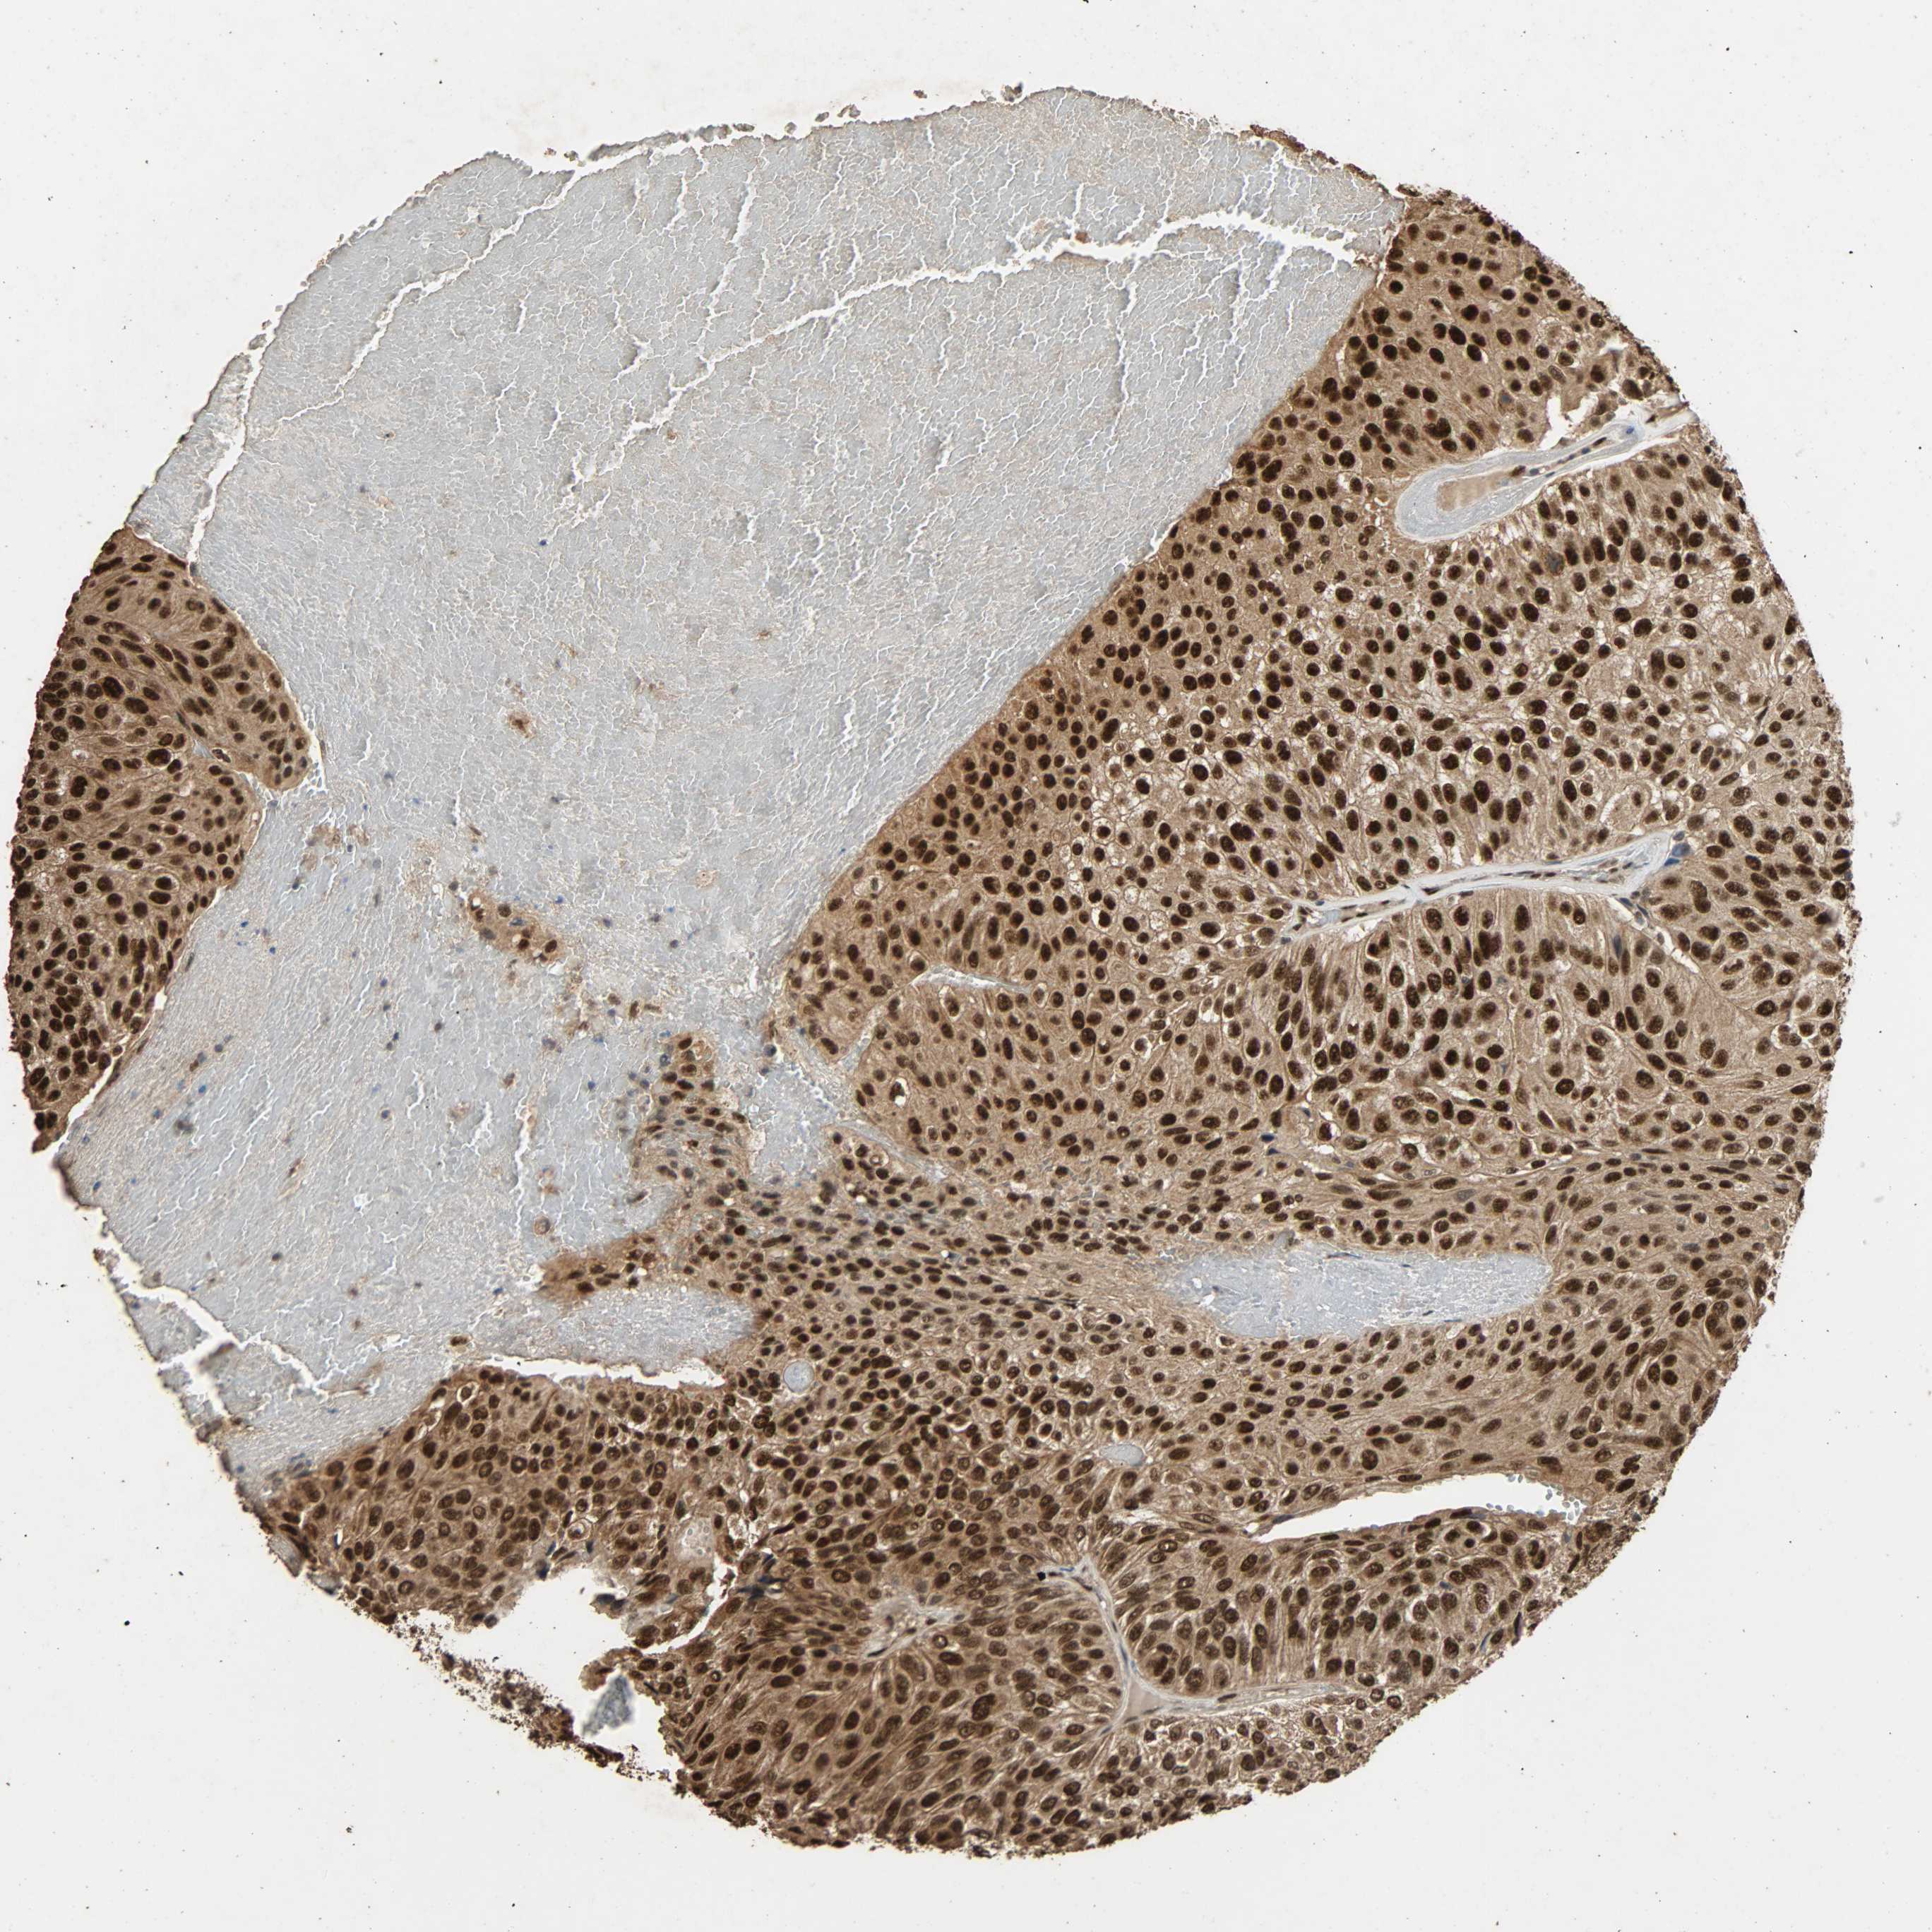

UROTHELIAL CANCER - Protein expressioni

A mouse-over function shows sample information and annotation data. Click on an image to view it in a full screen mode. Samples can be filtered based on level of antibody staining by selecting one or several of the following categories: high, medium, low and not detected. The assay and annotation is described here.

Antibody stainingi

Antibody staining in the annotated cell types in the current human tissue is reported as not detected, low, medium, or high, based on conventional immunohistochemistry profiling in selected tissues. This score is based on the combination of the staining intensity and fraction of stained cells.

Each image is clickable and will lead to virtual microscopy that enables deeper exploration of all samples and also displays staining intensity scores, fraction scores and subcellular localization as well as patient and tissue information for each sample.

Antibody HPA005559

Staining

High

Medium

Low

Not detected

Intensity

Strong

Moderate

Weak

Negative

Quantity

>75%

75%-25%

<25%

None

Location

Nuclear

Cytoplasmic/membranous

Cytoplasmic/membranous,nuclear

Urothelial carcinoma, High grade

Urothelial carcinoma, Low grade